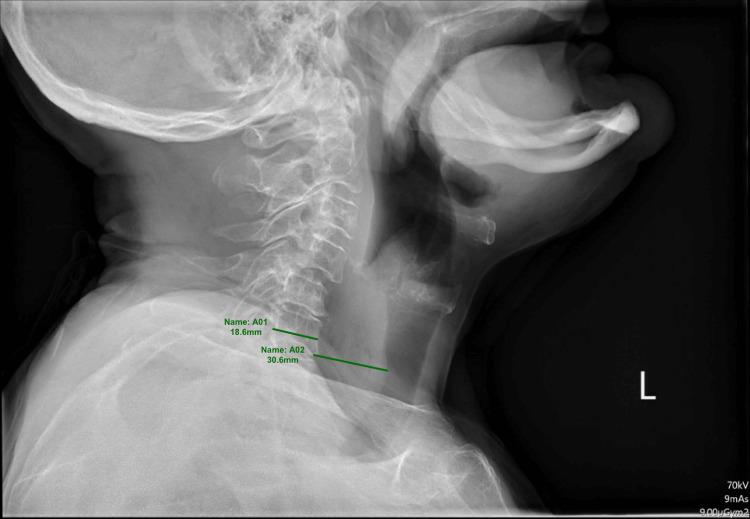

In this case, a 76-year-old female presenting with globus sensation post-oral intake demonstrated radiographical evidence of mottled radiolucency and prevertebral widening on a lateral neck X-ray at the inferior C4/cricoid cartilage, leading to concern for a prevertebral abscess. A decision was made to proceed with an urgent gastrointestinal endoscopy, and a food bolus was identified and removed, leading to a full remission of the patients' symptoms. In this case, an appropriate diagnosis was achieved by combining multiple investigations, which highlights to clinicians that taking investigations in isolation, with the aforementioned lateral neck X-ray being the primary example, could lead to potential misdiagnosis and mismanagement of patients.

在该病例中,一名76岁女性在进食后出现咽部异物感,颈部侧位X线片显示C4椎体下缘/环状软骨水平有斑点状透光影及椎体前缘增宽,提示可能存在椎前脓肿。于是决定紧急进行胃肠内镜检查,发现并取出了食物团块,患者症状完全缓解。在此病例中,通过综合多项检查做出了正确诊断,这向临床医生强调,孤立地进行检查,如上述以颈部侧位X线片为例,可能会导致对患者的潜在误诊和不当处理。